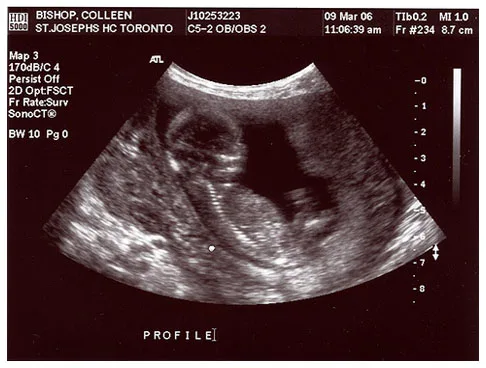

Чтобы выявить причину бесплодия, необходимо провести обследование. Далее, в зависимости от результатов обследования, назначается лечение, которое может быть оперативным или медикаментозным.

Результативное лечение бесплодия в Германии включает в себя проведение тщательного обследования обоих партнеров. Немецкие гинекологи в своей практике используют самые современные методы диагностики, будь то инструментальные и лабораторные тесты, или обследования на первоклассном оборудовании с 3 D эффектом.